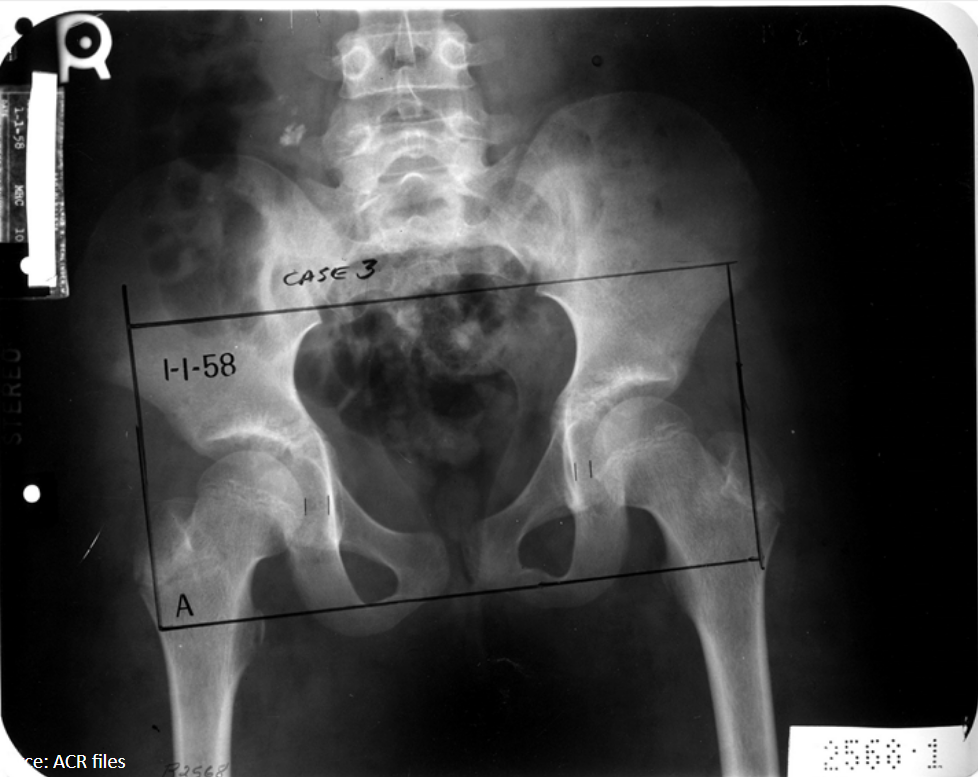

11

Q

What radiographic sign is present?

What does this mean by definition?

A

Waldenstrom’s sign: uneven hip joint space (one is increased) due to joint capsule swelling laterally displacing the femur

AVN of femoral capital epiphysis: LCP

12

12-year-old female presents with hip pain that refers to the knee.

Based on the evidence of avascular necrosis in her femoral capital epiphysis, what is the diagnosis?

Legg-Calve-Perthes (LCP)

Waldenstrom sign present